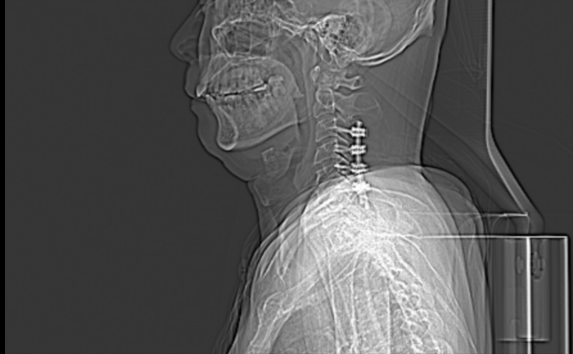

严先生入院后,骨科中心三区为其完善了相关检查,颈椎MRI提示:1.C3/4、C4/5、C5/6、C6/7椎间盘向后突出,伴后纵韧带增厚,继发椎管狭窄,颈髓受压并局部水肿。2.颈椎及椎间盘退行性变;急性颈脊髓损伤并不全瘫痪(ASIA C级)、颈椎管狭窄症、颈椎后纵韧带骨化症诊断明确,合并有四肢神经损伤症状、体质。

经与严先生及其家属沟通,骨科中心三区由柯绍强副主任医师带领胡海生主治医师及相关手术人员在全麻下为其顺利施行了“颈椎后路C3-6全椎板切除减压椎板植骨融合侧块钉棒内固定术”,术程顺利。严先生术后经过骨科中心三区医护团队的精心治疗和护理,实现自行独立行走,整体情况恢复良好。